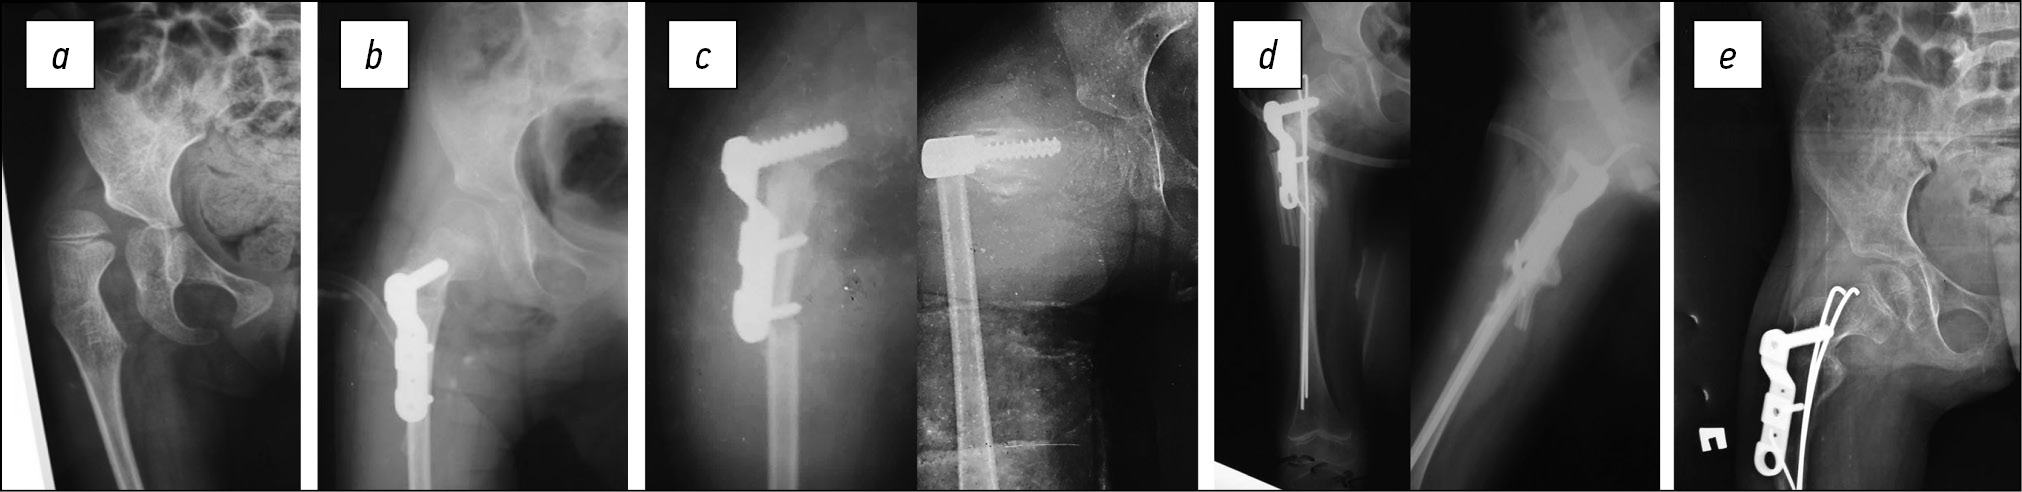

Ребёнок, 8 лет, IV уровень по GMFCS, оперирована по поводу вывиха правого тазобедренного сустава. Индекс массы тела варьировал от 16,8 кг/м2. Ремиссия по эпилепсии 2,5 года. Терапию отменили. Во время вертикализации ребёнок упал на пол с небольшой высоты. На рентгенограмме перелом бедренной кости на границе накостной пластины. Учитывая нестабильное положение отломков, неполную консолидацию в области остеотомии, нами был предложен оригинальный способ остеосинтеза: дистальный винт удалён, ретроградно выполнен остеосинтез эластичными титановыми стержнями до проксимального винта, концы стержней были ориентированы для поддержания оси бедра. Иммобилизация гипсовой повязкой на 4 недели позволила достичь консолидации и сращения перелома без потери коррекции (рис. 4).

Рис. 4. Перелом на границе накостной пластины у девочки 8 лет, рентгенограммы: a — перед реконструктивной операцией; b — после деротационно-варизирующей остеотомии; c — перелом бедра через 8 месяцев после операции; d — введение эластичных стержней для репозиции и фиксации перелома; e — через 1 год: костное сращение и ремоделирование, результат реконструктивного вмешательства также сохраняется

Fig. 4. Fracture at the border of the bone plate in an 8-year-old girl, radiographs: a — before reconstructive surgery; b — after derotational-variation osteotomy; c — hip fracture 8 months after surgery; d — insertion of elastic rods for repositioning and fixation of the fracture; e — after 1 year: bone fusion and remodeling, the result of reconstructive intervention is also preserved